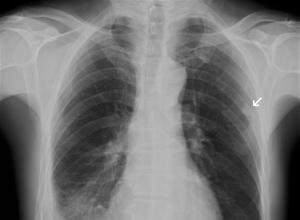

根据身体其他部位的化脓性感染,胸骨出现肿痛。结合胸部X线肋骨骨质破坏可明确诊断。

血常规检查白细胞计数升高,中性粒细胞比例增高,胸部X线检查见病变肋骨局部增粗,骨质溶解破坏,可有胸膜反应征象。如治疗不及时,脓肿可向外穿破皮肤形成窦道,向内穿破胸膜形成脓胸。病程进入慢性期,皮肤上可有反复发作的窦道、有死骨形成。根据身体其他部位的化脓性感染,胸骨出现肿痛,结合胸部X线肋骨骨质破坏可明确诊断。